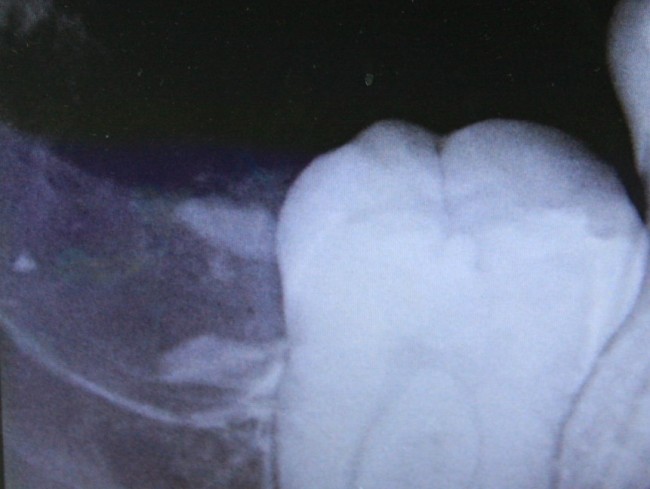

Делаем контрольный снимок, чтобы убедиться в том, что мы не повредили семерку:

И все. Вся эта работа заняла, максимум, 15 минут. Если кто-то в этом сомневается, есть два варианта проверить: